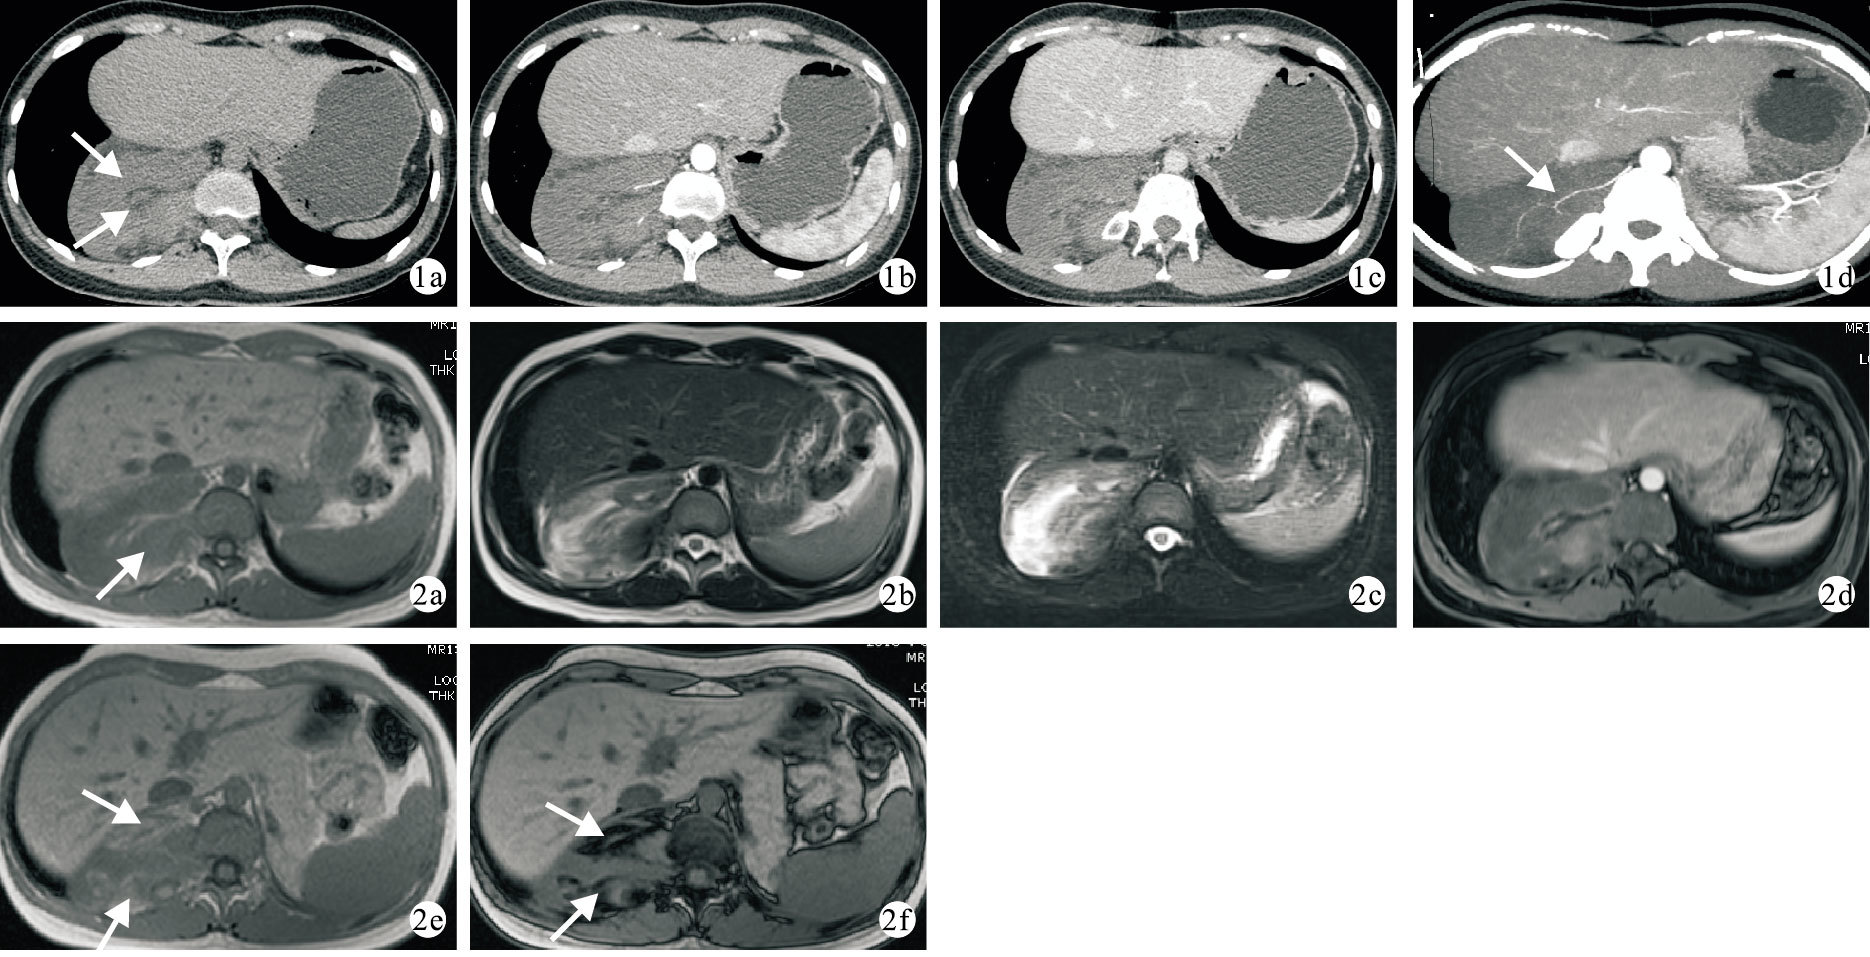

CT檢查提示:右側后下縱隔脊柱旁見混雜密度腫塊,大小約10 cm×7 cm×10 cm,平掃腫塊內部見少許脂肪密度,其余為軟組織密度(圖 1a);增強后腫塊呈輕度不均勻強化,鄰近椎間孔稍顯擴大,右側第12肋骨近段膨大并受壓彎曲(圖 1b,1c),最大密度投影(MIP)上可見腫塊供血動脈(圖 1d)。MRI平掃T1WI腫塊呈等信號(圖 2a),T2WI及T2壓脂呈不均勻高信號(圖 2b,2c),增強掃描腫塊不均勻輕度強化(圖 2d),同相位腫塊內可見條片狀高信號(圖 2e),反相位呈低信號(圖 2f),病變與椎間孔關系密切,鄰近椎間孔稍擴大,增強后期輕度不均勻強化。